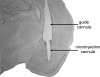

Figure 10.

Representative photomicrograph showing guide cannula placement dorsal to the amygdala and microinjection cannula placement in the amygdala. Microinjections were administered bilaterally, and microdialysis samples were collected from the right amygdala.